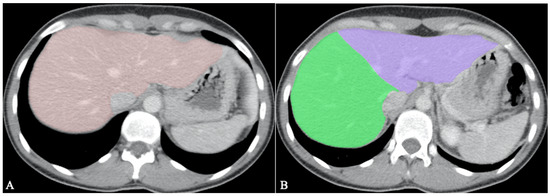

- Lim, M.C.; Tan, C.H.; Cai, J.; Zheng, J.; Kow, A.W.C. CT volumetry of the liver: Where does it stand in clinical practice? Clin. Radiol. 2014, 69, 887–895. [Google Scholar] [CrossRef]

- Jimenez-Pastor, A.; Alberich-Bayarri, A.; Lopez-Gonzalez, R.; Marti-Aguado, D.; França, M.; Bachmann, R.S.M.; Mazzucco, J.; Marti-Bonmati, L. Precise whole liver automatic segmentation and quantification of PDFF and R2* on MR images. Eur. Radiol. 2021, 31, 7876–7887. [Google Scholar] [CrossRef] [PubMed]